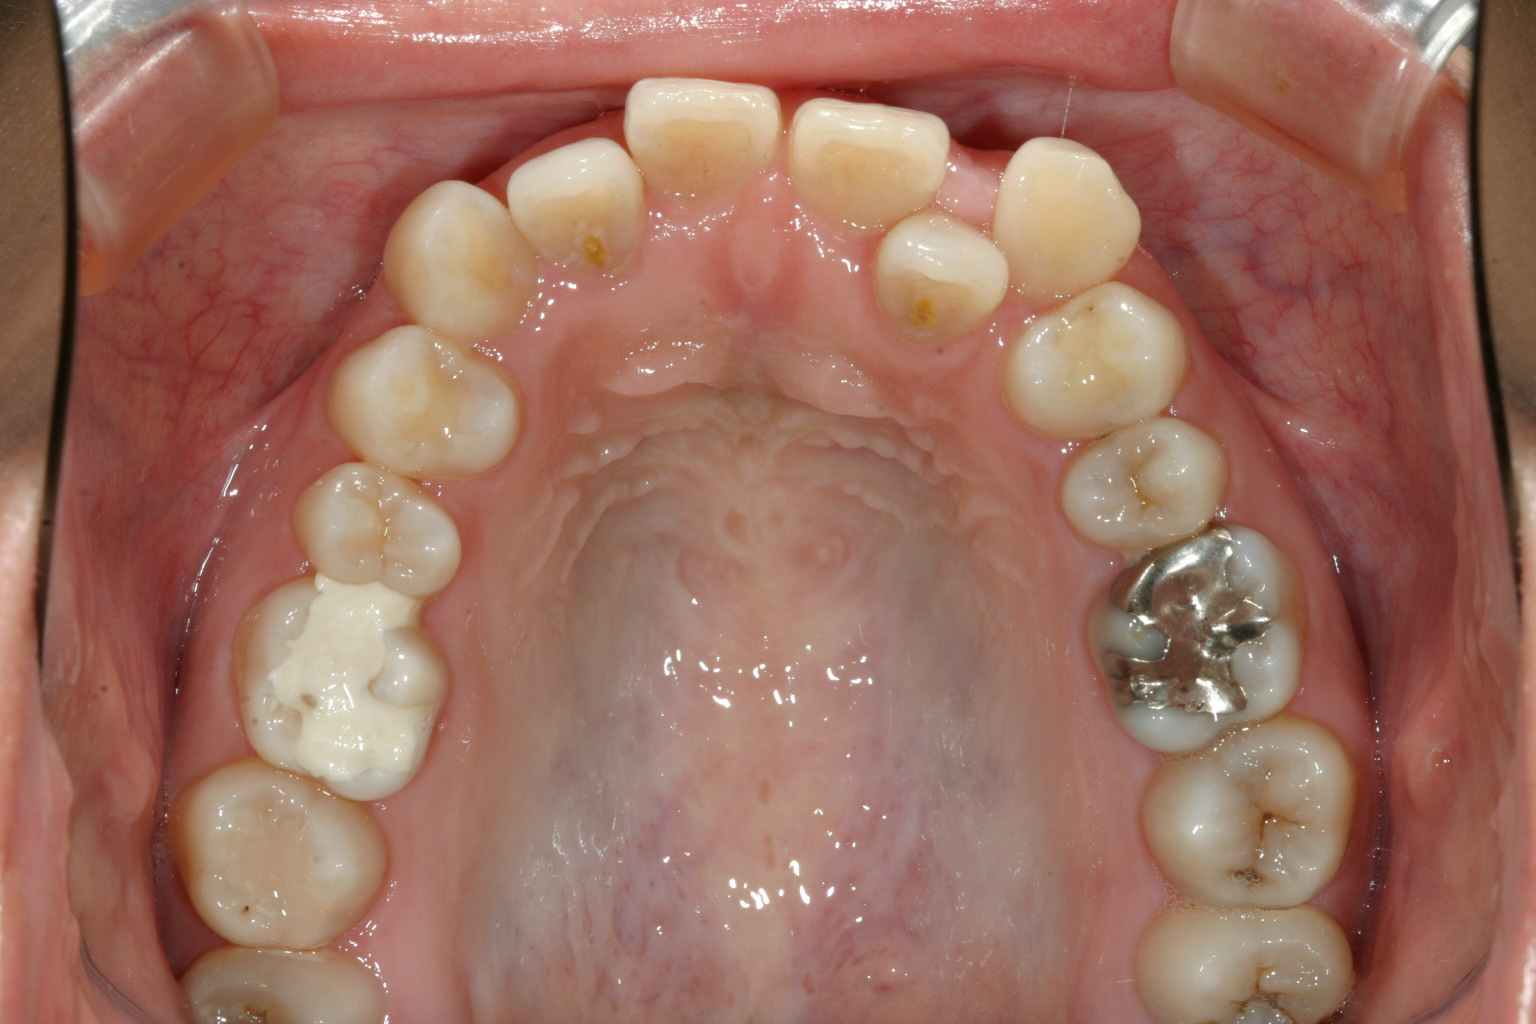

特に左側の犬歯が飛び出した感じになっています。

歯列が内側に傾斜してアーチが狭くなり前歯に ガタガタが生じています。

今回のケースは上顎の2番目の前歯が内に入った為犬歯が飛び出したようになっています。

それはすべてアーチが狭い為にそのしわ寄せが前歯に影響しています。